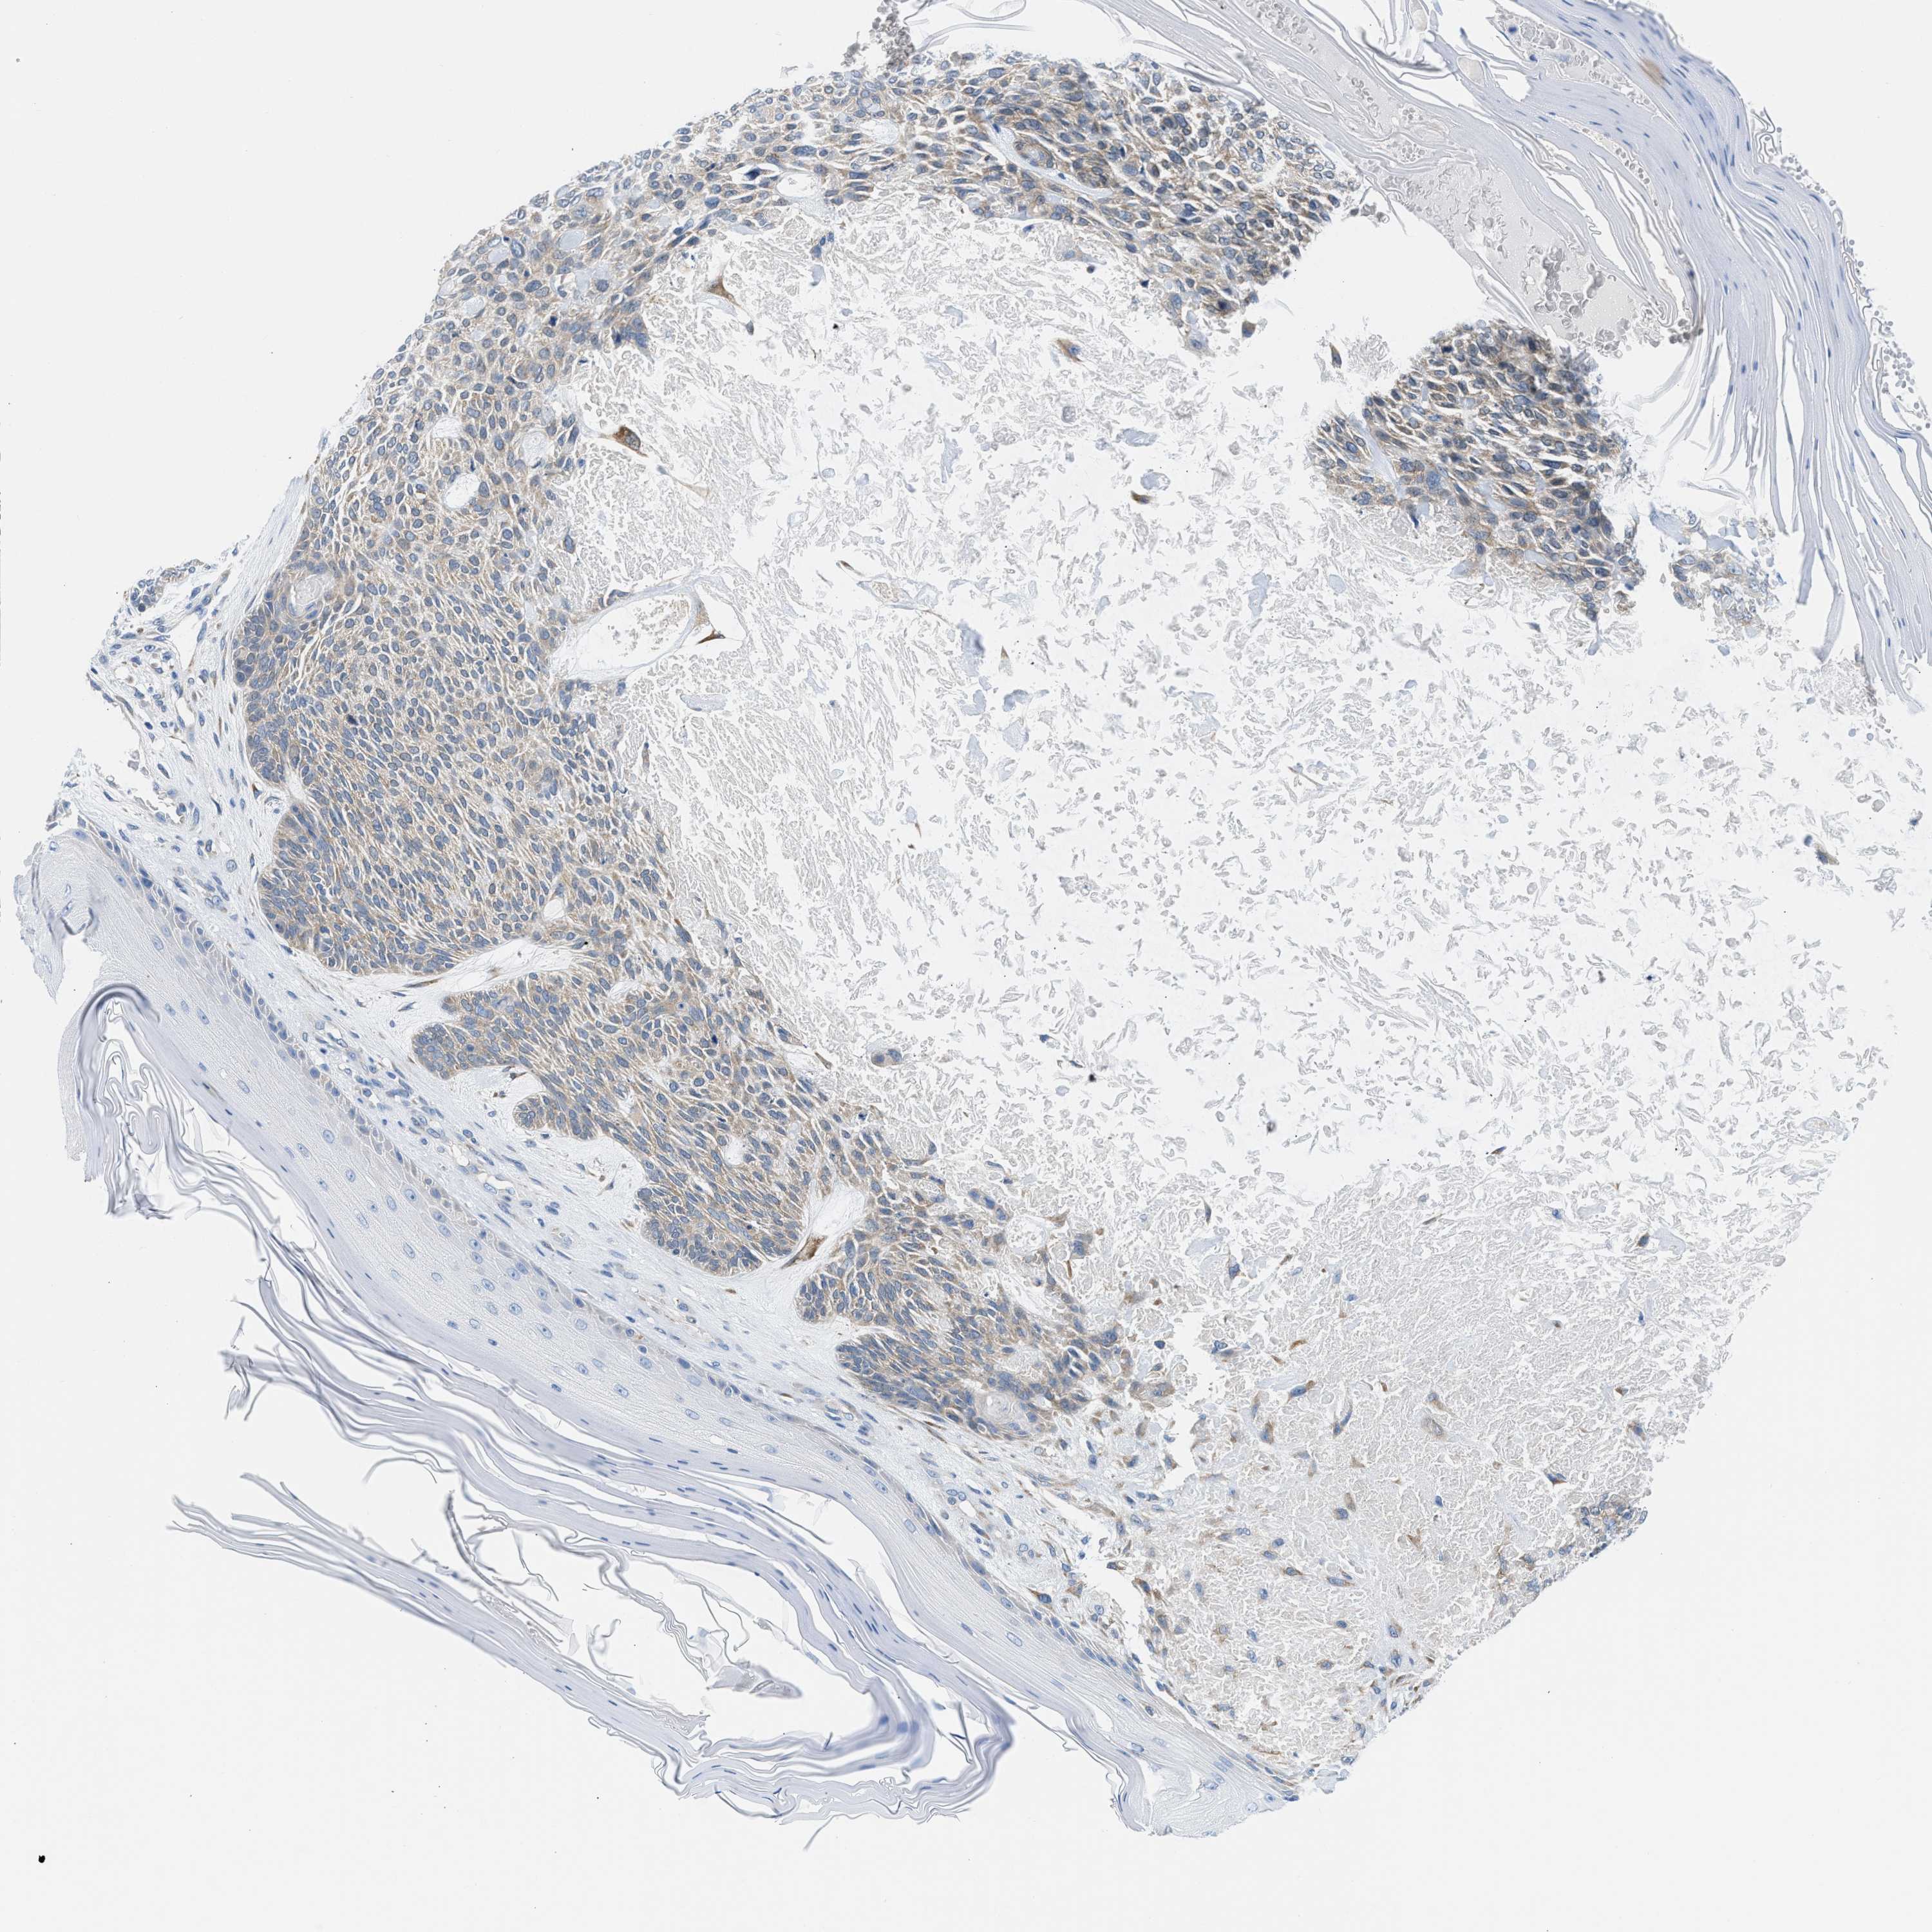

SKIN CANCER - Protein expressioni

A mouse-over function shows sample information and annotation data. Click on an image to view it in a full screen mode. Samples can be filtered based on level of antibody staining by selecting one or several of the following categories: high, medium, low and not detected. The assay and annotation is described here.

Antibody stainingi

Antibody staining in the annotated cell types in the current human tissue is reported as not detected, low, medium, or high, based on conventional immunohistochemistry profiling in selected tissues. This score is based on the combination of the staining intensity and fraction of stained cells.

Each image is clickable and will lead to virtual microscopy that enables deeper exploration of all samples and also displays staining intensity scores, fraction scores and subcellular localization as well as patient and tissue information for each sample.

Antibody HPA018525

Squamous cell carcinoma, NOS

Squamous cell carcinoma, metastatic, NOS

Basal cell carcinoma